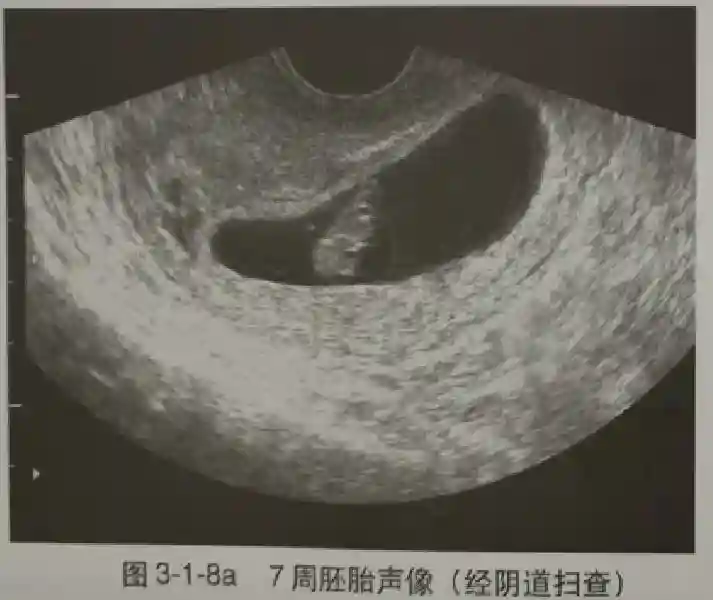

3??胚胎:胚胎通常在6-7周时可以为超声显示,起初为胎芽,表现为卵黄囊一侧局部组织增厚,达到1 -2 mm 时才有可能为超声测量出来。达4-5mm时可见胎心搏动,相应孕周为6-6.5周,妊娠囊大小为13-18mm。胚芽长度≥7㎜时仍未见心管搏动,提示胚胎停止发育。胚胎的出现和妊娠囊直径的关系:妊娠囊直径> 16 mm 时,经阴道超声应显示胚胎。妊娠囊直径> 25 mm 时,经腹超声均应显示胚胎。

4??胎心搏动:胎心搏动通常出现于6-6.5周,胚胎在4- 5mm就应该显示胎心搏动。